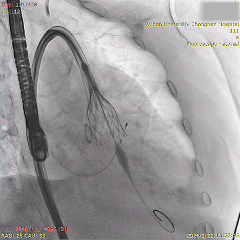

最终造影可见瓣膜形态佳、位置理想,冠脉良好,无明显瓣周漏

术后超声影像

左室长轴超声无明显反流

二尖瓣反流可见改善